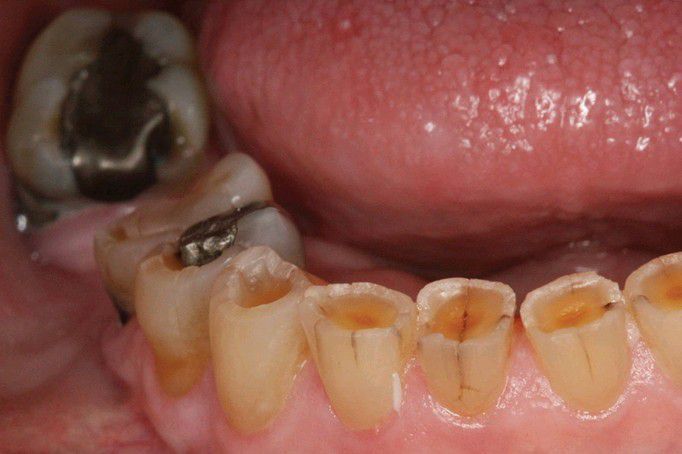

Erosion

Multiple mandibular anterior teeth exhibiting depressions of dentin surrounded by elevated rims of enamel. Note the amalgam in the first bicuspid that is raised above the surface of the surrounding depressed dentin.